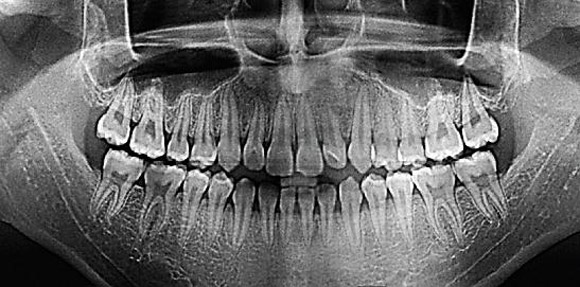

Панорама (ортопантомограмма, ОПТГ, панорамный снимок челюстей) – это обзорный круговой снимок зубов, при котором видна вся челюсть, развернутая в двухмерной плоскости. Она может быть цифровой и пленочной.

Панорамный снимок (или ортопантомограмма) – это плоское двухмерное изображение челюстей, зубов, гайморовых пазух и даже височно-нижнечелюстного сустава. Поскольку поверхность челюстей изогнутая, на плоской рентгеновской плёнке снимок отображается неравномерно увеличенным в боковых и передних отделах челюстей – то есть слегка деформированым.

- Много информации на одном снимке — видны все зубы с корнями, обе челюсти, гайморовы пазухи, височно-нижнечелюстные суставы, частично даже полость носа.